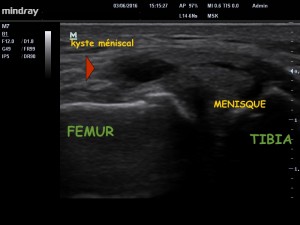

Une semaine après l’électrolyse le patient ne présente plus cette induration douloureuse. L’échographie démontre une nette diminution de la taille du kyste (image 4) , une nouvelle électrolyse est alors réalisée. Le reste de la prise en charge a consisté en une approche fonctionnelle centrée sur le soutien musculaire et ligamentaire du genou, et en une amélioration de contrôle moteur par un suivi en réhabilitation.

image 4. Nette diminution de la taille du kyste à J7.